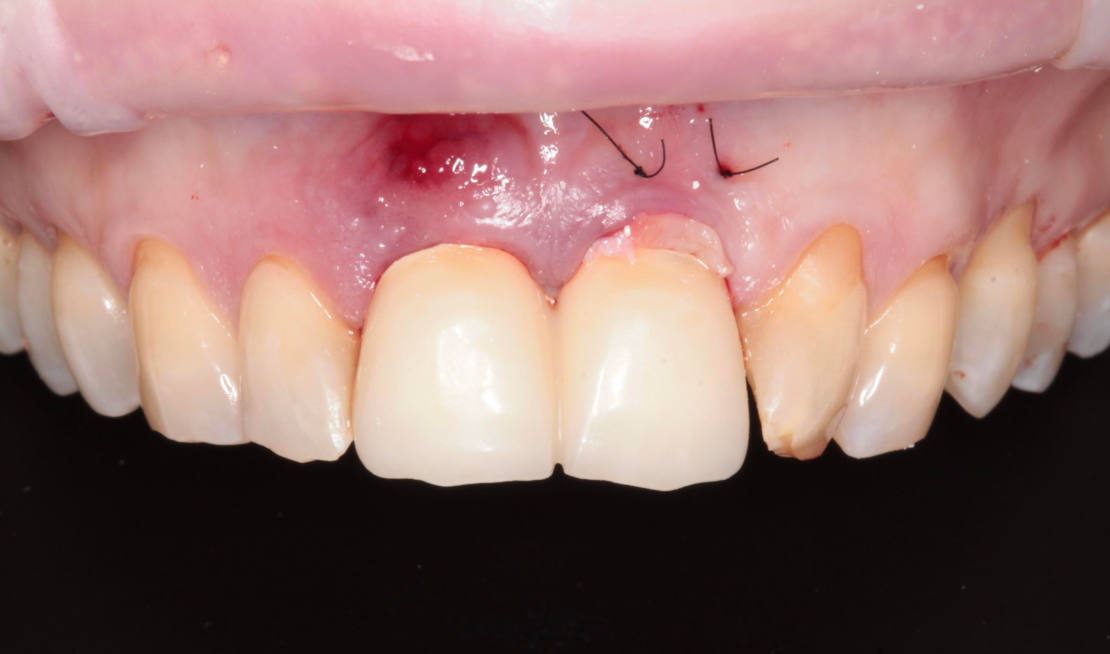

45-ročná pacientka sa obrátila na našu kliniku s bolesťou v oblasti horných stredných rezákov (obr. 1). Pri dôkladnom vyšetrení a CT diagnostike bola v oblasti zuba č. 11 zistená vertikálna fraktúra koreňa (obr. 2). V oblasti zuba č. 21 palatinálne bol prítomný hlboký kaz koreňa (obr. 3).

Jediným riešením bola extrakcia obidvoch zubov. Najväčšou obavou zo strany pacientky bola strata obidvoch predných zubov a následného fungovania bez nich pri práci s ľuďmi. Ideálnym riešením teda bola náhrada zubov implantátmi spolu s nasadením koruniek, a to počas jedného sedenia. V deň konzultácie bol pacientke urobený sken pomocou intraorálneho skeneru 3Shape TRIOS, ktorý nám umožňuje zobraziť 3D simuláciu ústnej dutiny. Pomocou softwaru 3Shape Implant Studio sme spojili dáta z intraorálneho skenu a CBCT, STL a DICOM súbory. V ďalšom kroku sme virtuálne vložili implantáty v správnej protetickej polohe, navrhli šablónu pre ich zavedenie, namodelovali individuálne abutmenty a korunky (obr. 4). Kompletné dáta sme exportovali pre frézovanie a 3D tlač. V laboratóriu sa pomocou 3D tlačiarne vytlačila chirurgická šablóna, ktorá nám slúži na presné zavedenie implantátov – použili sme implantačný systém Dentium Super Line. Následne boli vyfrézované zirkonové abutmenty a plastové dočasné korunky(obr. 5).

Vďaka týmto postupom bola operácia veľmi rýchla a pacientka odišla z ordinácie plne rehabilitovaná. Minimálne invazívnym spôsobom boli extrahované horné jednotky (obr. 6).